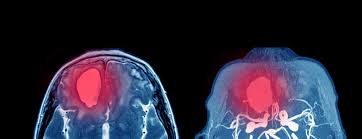

Brain Aneurysm - Risk Factors Of Brain Aneurysms / Aneurysms often form at forks or branches in arteries because those sections of the.. Aneurysms are usually found at the base of the brain just inside the skull, in an area called the subarachnoid space. When a brain aneurysm ruptures, this is called a subarachnoid hemorrhage (sah). A brain aneurysm is a weak spot in a blood vessel that bulges and fills with blood. A brain aneurysm occurs when a weak spot in your brain's arterial wall bulges and fills with blood. A brain aneurysm can result from a congenital defect, some inherited diseases, or other degenerative conditions, such as hypertension (high blood pressure) or atherosclerosis (fat buildup inside the arteries, often leading to heart attack or stroke).

How Aware Are You Brain Aneurysm Awareness Quiz Brain Aneurysm Foundation from bafound.org An intracranial aneurysm, also known as a brain aneurysm, is a cerebrovascular disorder in which weakness in the wall of a cerebral artery or vein causes a localized dilation or ballooning of the blood. Brain aneurysms are also called cerebral aneurysms or intracranial aneurysms. A brain or cerebral aneurysm is a cerebrovascular disorder that is caused when the wall of an artery in the brain becomes weak and balloons outward. A brain aneurysm, also called a cerebral or intracranial aneurysm, is a spot of weakness of a brain artery. They are most common in adults between the ages of 30 and 60 and are more common in women cerebral aneurysms form when the walls of the arteries in the brain become thin and weaken. An aneurysm can leak or rupture, causing bleeding into the area around the brain (subarachnoid hemorrhage). Typically, these aneurysms are small. Brain aneurysm or cerebral aneurysm is a ballooning or a bulge in a blood vessel inside the human brain.

Other risk factors include cigarette smoking. A brain aneurysm can result from a congenital defect, some inherited diseases, or other degenerative conditions, such as hypertension (high blood pressure) or atherosclerosis (fat buildup inside the arteries, often leading to heart attack or stroke). Learn about symptoms such as the worst headache of your life, pain or stiffness in the neck. Aneurysms are usually found at the base of the brain just inside the skull, in an area called the subarachnoid space. Brain aneurysm or cerebral aneurysm is a ballooning or a bulge in a blood vessel inside the human brain. This leads to an extremely serious condition known as a subarachnoid haemorrhage, where bleeding caused by the ruptured aneurysm can cause extensive brain damage and symptoms. However, brain aneurysms are actually a fairly regular occurrence and. Brain aneurysms can occur in anyone and at any age. They are sometimes called berry aneurysms because they are often the size of a small berry. A ruptured aneurysm releases blood into the subarachnoid space around the brain. An aneurysm can leak or rupture, causing bleeding into the area around the brain (subarachnoid hemorrhage). Every year, hundreds of patients with even the most complex brain aneurysms experience our collaborative approach, decades of experience and access to the full range of modern technologies, delivered with care and compassion. Most brain aneurysms only cause noticeable symptoms if they burst (rupture).

Most people with brain aneurysms have no symptoms. 31,879 likes · 687 talking about this · 353 were here. Brain aneurysms (also called cerebral aneurysms or intracranial aneurysms) are a weakness in a blood vessel of the brain that leads to a bubble or bulge that can rupture or bleed. Most often a ruptured brain aneurysm occurs in the brain aneurysms develop as a result of thinning artery walls. A brain aneurysm is an abnormal bulge or ballooning in the wall of an artery in the brain.